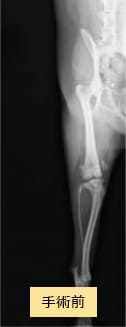

チワワ×マルチーズ(4歳10ヶ月齢、雌)グレードU〜V 外科手術

- 【初診時症状】

- 他院にて両後肢パテラグレードVと診断

手術を希望されて受診

- 【手術】

- 滑車溝形成術、脛骨粗面転位術、関節包縫縮を実施

- 【経過】

- 性格的にご自宅での安静が難しいため、術後2週間入院。術後4週間で屋内での運動制限を徐々に解除、8週間でお散歩の距離を少しずつ伸ばしていくも問題なし。

現在は制限なく生活